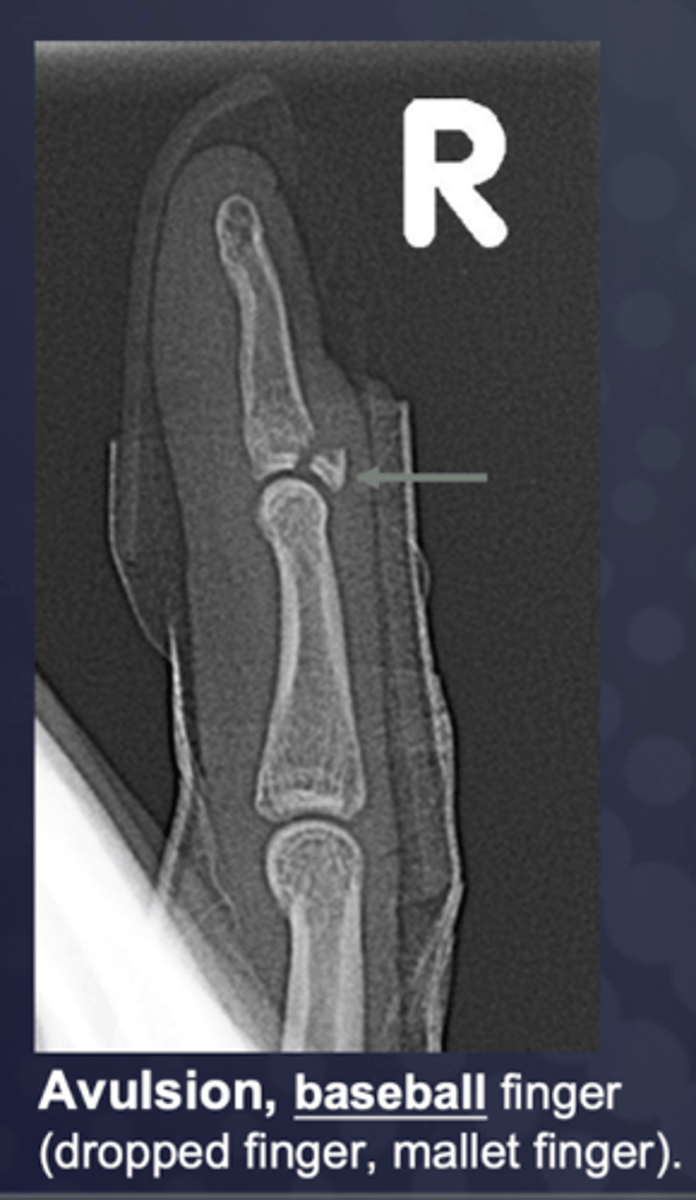

________: type of bone fracture that occurs when a ligament or tendon forcefully pulls a small piece of bone away from the main bone mass

Avulsion (occurs at the site of musculotendinous and ligamentous attachments)